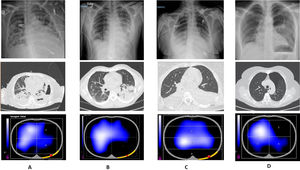

Thoracic images are presented through chest radiographs, electrical impedance tomography (EIT), and computed axial tomography in patients with pleuropulmonary disease (Fig. 1). A shows a loculated hydropneumothorax; EIT demonstrates reduced pulmonary volume distribution in quadrants 2 and 4, corresponding to the left lung. B shows a pulmonary contusion with left basal pleural effusion; EIT demonstrates absence of ventilation in quadrant 4, representing the left basal pulmonary region. C shows a bilateral pleural effusion; EIT is displayed in layers, denoting absence of ventilation in layer 4. D shows a left apical pneumothorax; EIT demonstrates absence of pulmonary volume distribution in quadrant 2.